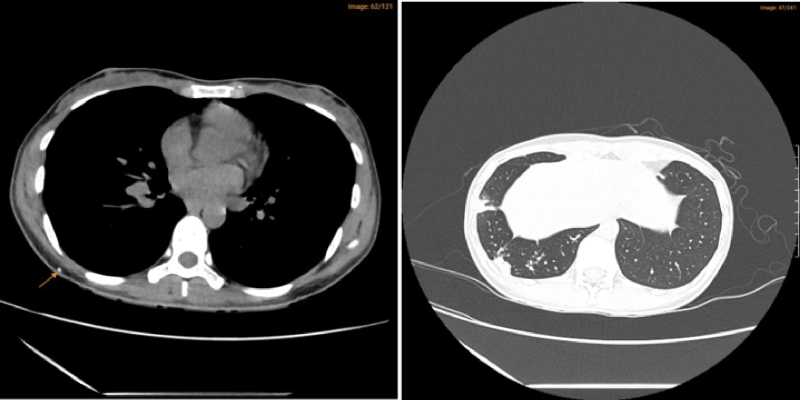

Bệnh nhân được bác sĩ chỉ định thực hiện chụp cắt lớp vi tính lồng ngực phát hiện hình ảnh tổn thương đông đặc, nốt đặc thùy dưới phổi phải, nốt đặc nhỏ thùy dưới phổi trái. Kết quả này cho thấy chị T. có hình ảnh viêm phổi chưa loại trừ tổn thương lao phổi cần phải làm xét nghiệm tìm tác nhân gây bệnh bao gồm vi khuẩn thông thường và vi khuẩn lao.

Hình ảnh chụp cắt lớp vi tính lồng ngực liều thấp của bệnh nhân